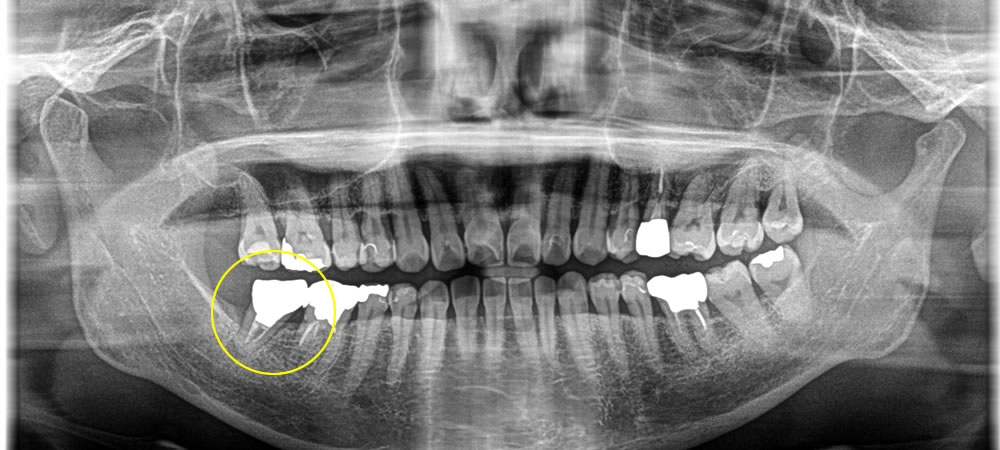

レントゲン検査の結果、過去に他院にて神経の治療を行った歯の根の先端に膿が溜まっていることが分かりました。

根尖が細菌感染を起こしていたため、CT撮影にてその範囲を確認したところ、広範囲に広がっており、再根管治療を行っても成功率が100%ではないこと、治療の回数がかかってしまうことを患者さまにお伝えしたところ、治療回数が比較的少なく、成功率が高いインプラントでの治療をご希望されました。